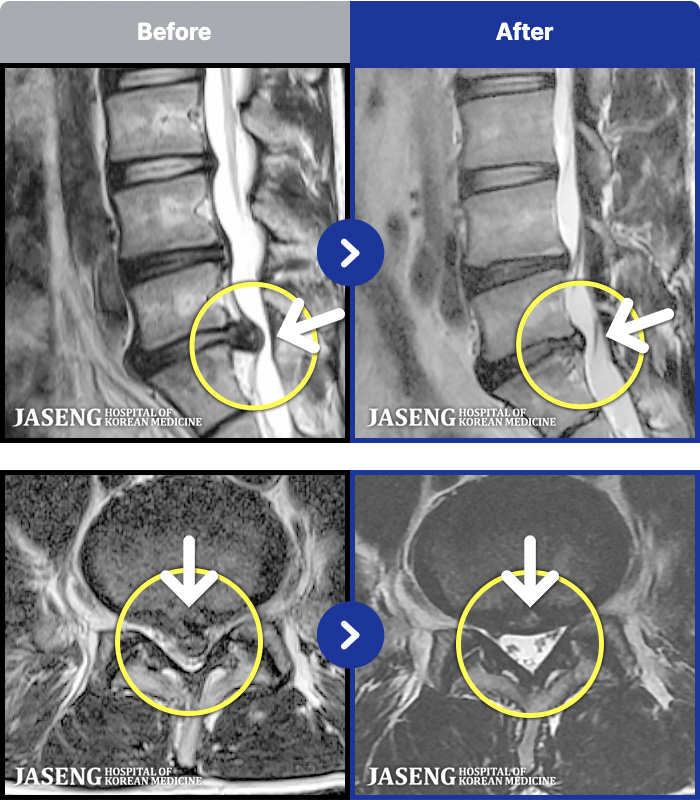

- MRI ġ

MRI ġ

1,240 MRI ũ ʸ Ȯϼ.